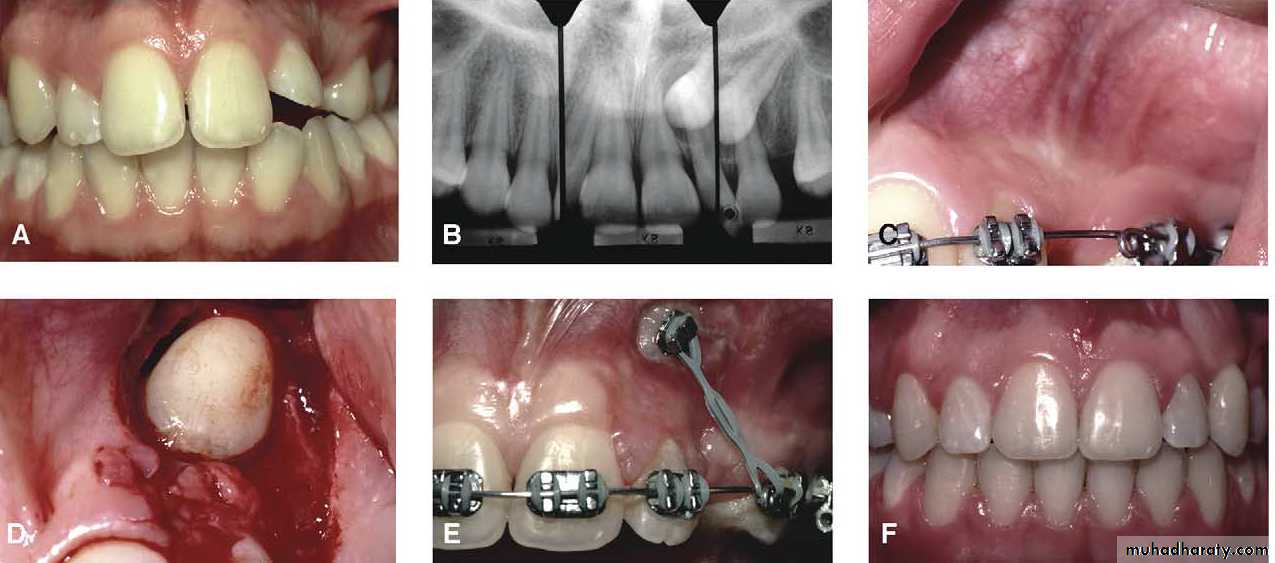

Transplantation and surgical repositioning

The success rate with transplantation is highest for1- unerupted teeth which have open apices because of the possibility of revascularization .

2- It is essential to establish that there is sufficient space to accommodate the canine crown. minimal space deficiency may be overcome by grinding of the crown , but otherwise orthodontic therapy may be required to move the premolar distally .

3-The canine should be extracted carefully and

transferred to the surgically prepared socket in the dental arch with the minimum of delay.It is preferable that the root surface should not be touched either with instruments or fingers as the viability of the cementum and periodontal membrane remnants will determine the success of the transplant. The tooth is stored under the flap to keep the tooth moist until the new socket is prepared .

Root filling is not attempted so as to reduce handling of the tooth .

4- The transplanted tooth should be splinted in its new position for a month after the operation .Surgical repositioning